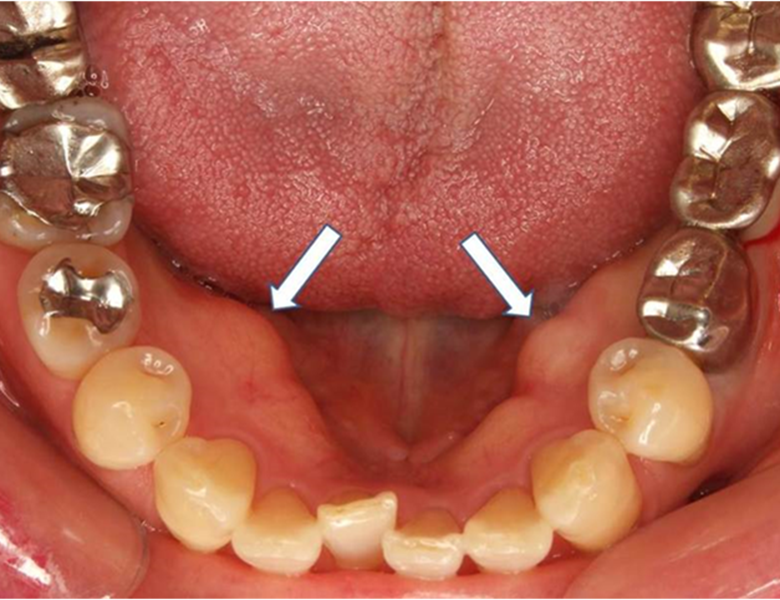

歯茎や上顎の「硬い」コブ(骨隆起)

歯茎の横や、上顎の真ん中あたりにある、非常に硬い(骨のような)盛り上がりです。

病気ではなく、強い噛み合わせの力が加わることで、骨が反応して盛り上がった「骨の塊」です。

数年かけてゆっくりと大きくなり、表面を触っても痛みはありません。粘膜の色も周囲と同じです。

当院の対応

基本的には放置して問題ありませんが、入れ歯を入れる際に邪魔になったり、表面の皮が薄いため傷つきやすかったりする場合は、切除を検討することもあります。

まずは「病気ではない」という診断で安心していただけるケースが多いです。